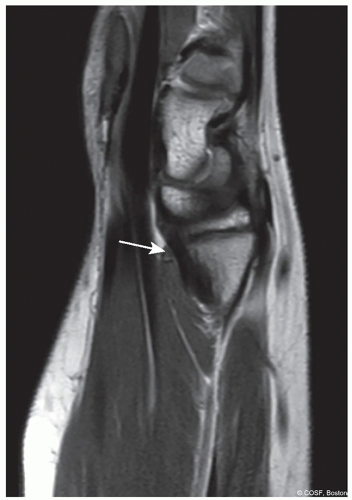

Figure 15-5 ▪ MRI appearance of Vickers ligament. (Courtesy of Children’s Orthopaedic Surgery Foundation.)